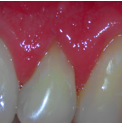

Surgical Exposure of ECIR with External Cervical Root Repair, Conventional RCT with Prefab Post

All Treatment performed by Dr. Brian A. Christopherson